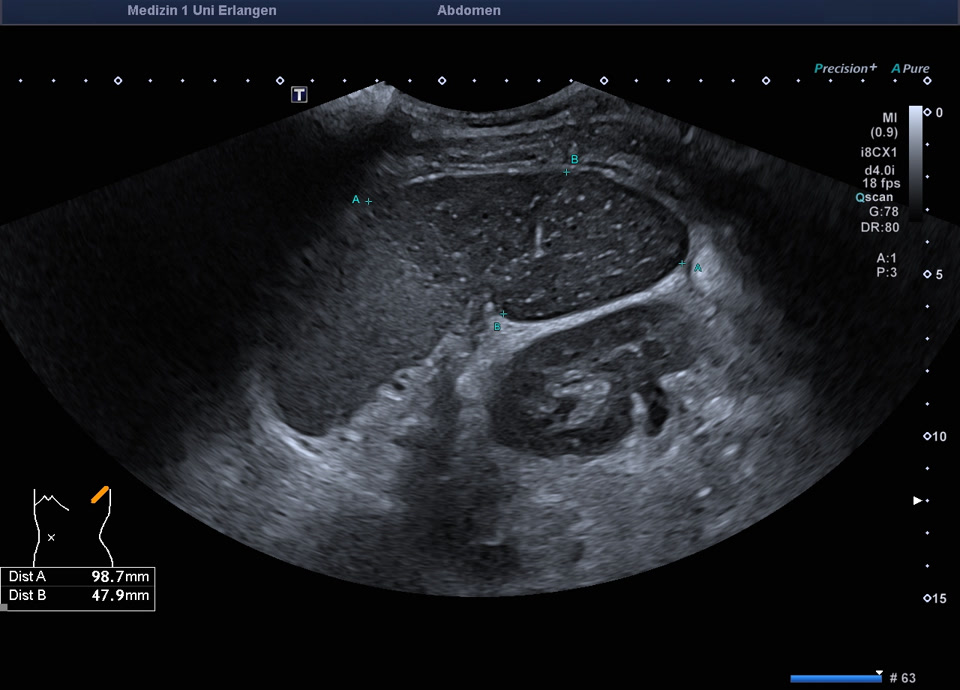

Epikrise: 19-jährige Patientin mit einem schweren angeborenen Herzfehler berichtet über plötzlich aufgetretene starke Schmerzen in der linken Flanke vor 14 Tagen. Sonographisch zeigt sich die Milz regelrecht lokalisiert, mit einem ausgedehnten Milzinfarkt der unteren Milzhälfte. Weder im Farbdoppler, noch im CEUS, lässt sich eine Restperfusion der unteren Milzhälfte feststellen. Therapeutisch wird eine Antikoagualtion begonnen und eine Verlaufskontrolle in 4 Wochen veranlasst.